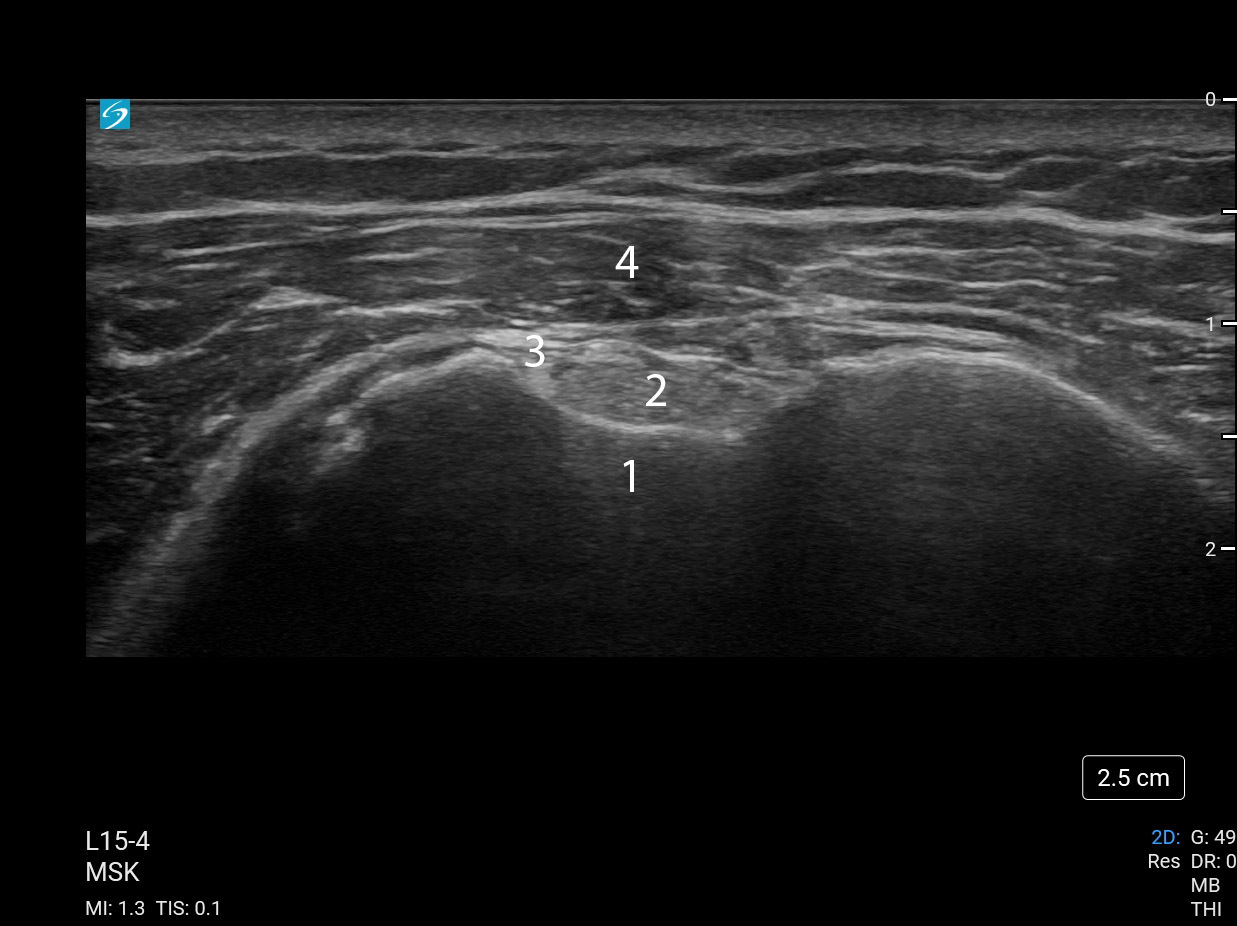

Shoulder Biceps Tendon Short Axis 1 (Sonosite PX L15-4) Image

1. Biceps Groove

2. Biceps Tendon

3. Ascending Branch of the Lateral Circumflex Humeral Artery

4. Anterior Deltoid Muscle